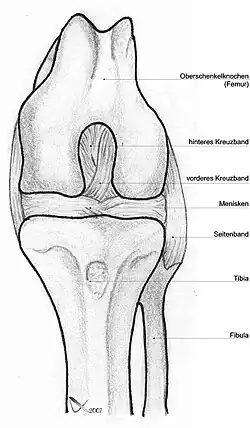

Das Kniegelenk (lateinisch Articulatio genus) ist das im Knie (lateinisch Genu, altgriechisch γόνυ gony) befindliche größte Gelenk der Säugetiere. Der Oberschenkelknochen (Femur), das Schienbein (Tibia) und die Kniescheibe (Patella) bilden dabei die knöchernen Gelenkkörper.

Das Kniegelenk ist ein zusammengesetztes Gelenk. Es besteht aus zwei Einzelgelenken, dem Kniescheibengelenk (Articulatio femoropatellaris), welches sich zwischen Oberschenkelknochen und Kniescheibe befindet, und dem Kniekehlgelenk (Articulatio femorotibialis), das zwischen Oberschenkelknochen und Schienbeinkopf (Caput tibiae) liegt. Anatomisch gesehen handelt es sich bei dem proximalen Gelenk zwischen Schienbein (Tibia) und Wadenbein (Fibula) (Articulatio tibiofibularis) zwar um ein eigenständiges Gelenk, das aber in der Regel über eine Ausbuchtung der Kniegelenkkapsel (Recessus subpopliteus) mit dem Kniegelenk verbunden ist.

Bänder

Da das Knie durch seine knöcherne Konstruktion sehr instabil ist, wird es durch zahlreiche Bänder gesichert. Sie verstärken damit die Gelenkkapsel, in deren äußere Schicht sie in der Regel eingebaut sind. Die Bänder des Knies werden nach ihrer Lage in vordere (ventrale), seitliche (kollaterale), hintere (dorsale) und zentrale Bänder eingeteilt.

Seitliche Bandsicherung

Das Knie hat zwei Seitenbänder: ein inneres (Ligamentum collaterale tibiale) und ein äußeres (Ligamentum collaterale fibulare). In Streckstellung sind beide Seitenbänder (auch Kollateralbänder genannt) gespannt und verhindern somit die Drehbewegung, in Beugestellung verkleinert sich der Krümmungsradius, Ursprung und Ansatz nähern sich einander an und die Bänder sind infolgedessen entspannt. Beide Seitenbänder stabilisieren das Kniegelenk in seitlicher Richtung (Frontalebene), damit ein Wegknicken in eine O-Bein-Stellung (Genu varum) oder X-Bein-Stellung (Genu valgum) verhindert wird.

Zentrale Bandsicherung

Die Kreuzbänder (Ligamenta cruciata) ziehen von der Grube zwischen den Oberschenkelknorren zum Schienbein. Von der Seite und von vorn betrachtet überkreuzen sie sich dabei in ihrem Verlauf.

Menisken

Da die miteinander in Verbindung stehenden (artikulierenden) Gelenkflächen nicht genau aufeinander passen, wird diese „Ungleichheit“ (Inkongruenz) durch halbmondförmige Faserknorpelscheiben, die Menisken ausgeglichen, die den Drehbewegungen folgen können. Eine weitere Aufgabe der Menisken besteht in der Vergrößerung der Kontaktfläche zwischen Schienbein und Oberschenkelknochen.

Man unterscheidet einen Innenmeniskus (Meniscus medialis), der C-förmig, größer und etwas unbeweglicher (da mit dem Innenband verwachsen) ist, und einen Außenmeniskus (Meniscus lateralis), der kreisförmig, kleiner und beweglicher ist (da er mit keinem Seitenband verwachsen ist). Die Menisken sind im Querschnitt keilförmig. Die hohe Kante liegt außen, die niedrige innen. Da die Oberschenkelknochen genau in der Mitte direkt auf dem Schienbeinplateau und peripher auf den Menisken aufliegen, tragen diese einen wesentlichen Teil der Last.